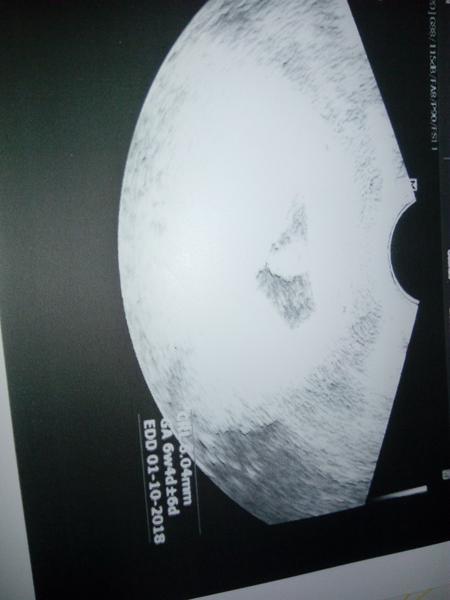

Ahoj tak u doktorky těhotenství potvrzeno, mimco velikosti odpovida a dostala jsem prukazku. Srdicko mi sice poslechnout nedala, vlastne ho ani nezminila, ale slova v prukazce jeden zivy plod mluvi jasne, kontrola za mesic a ještě se musim objednat na screening do gennetu, protoze jsem odmitla jit k Apolinari ze se tam bojim :D